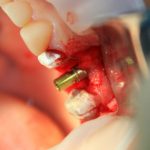

Синуслифтинг: что делать при перфорации слизистой оболочки гайморовой пазухи?